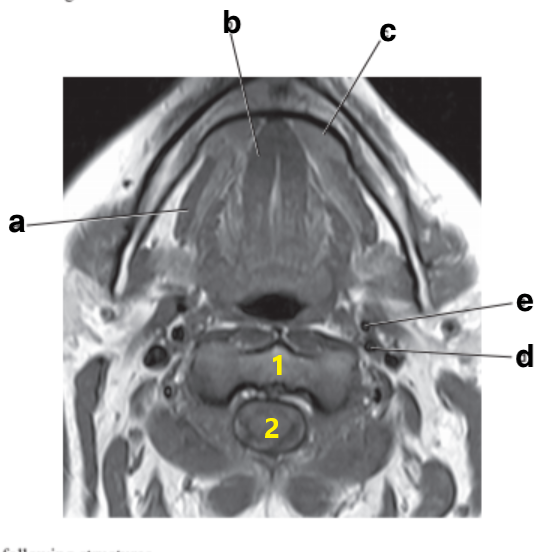

What is letter e?

Subclavian artery

What is letter b?

Thyroid gland

What is letter c?

Aortic arch

Mandible

Parotid gland

Trachea

Internal carotid artery

Cervical Spinal cord

Epiglottis

Submandibular gland